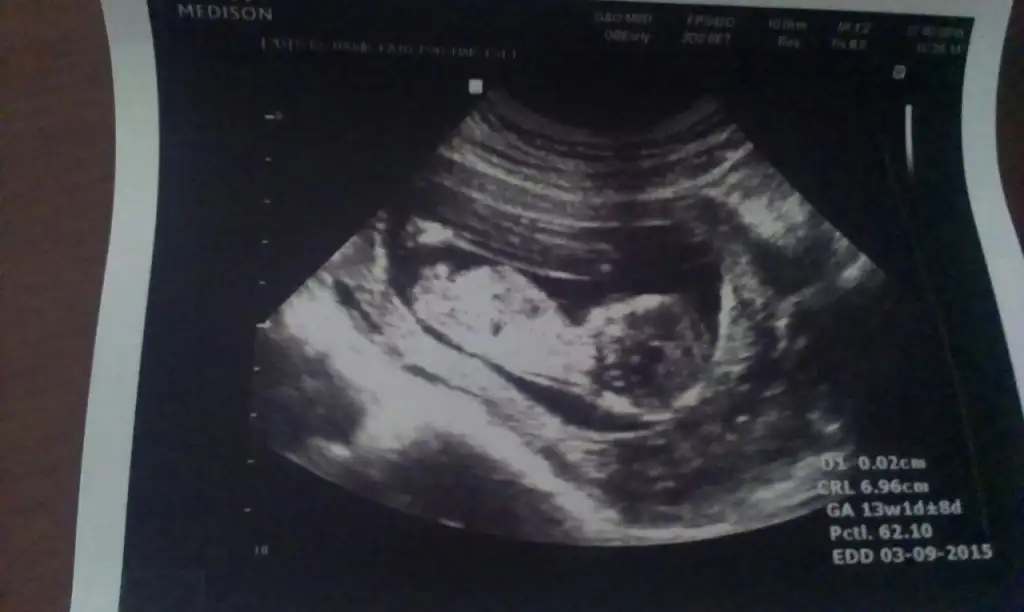

Kız geliyor annesi masallah kuzuna hayirlisiarkadaşlar lütfen benim bebeğim hakkında da yorum yapar mısınız? bebeğim şu an 13 haftalık, doktorum bilgi vermiyor erken olduğu için...